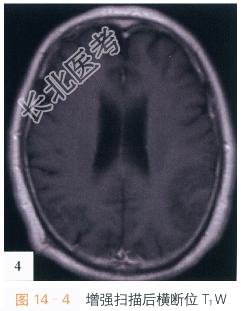

影像学资料:如图14-1~图14-4所示。

读片分析:头颅CT平扫,如图14-1所示,横断位示左颞叶见类圆形等高密度病灶,密度均匀、边界清楚,周围无明显水肿带,肿瘤临近蛛网膜下腔无增宽,脑沟脑回无受压或移位;头颅横断位MRI T₁W像,如图14-2,左颞叶类圆形低信号肿块影,内部信号稍欠均匀;邻近蛛网膜下腔无增宽,脑沟及脑回无明显受压移位;横断位T₂W像,如图14-3所示,肿块呈等高信号影,内部信号略不均匀,无明显囊变坏死及出血;增强扫描后横断位T₁W像,如图14-4所示,病灶强化稍欠均匀;病灶中必可见少许斑片状异常强化,余无明显异常强化,无脑膜尾征。